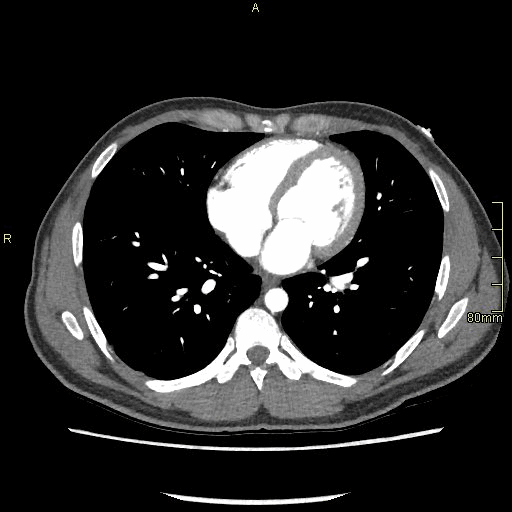

Abdomen Angiogram (Axial)